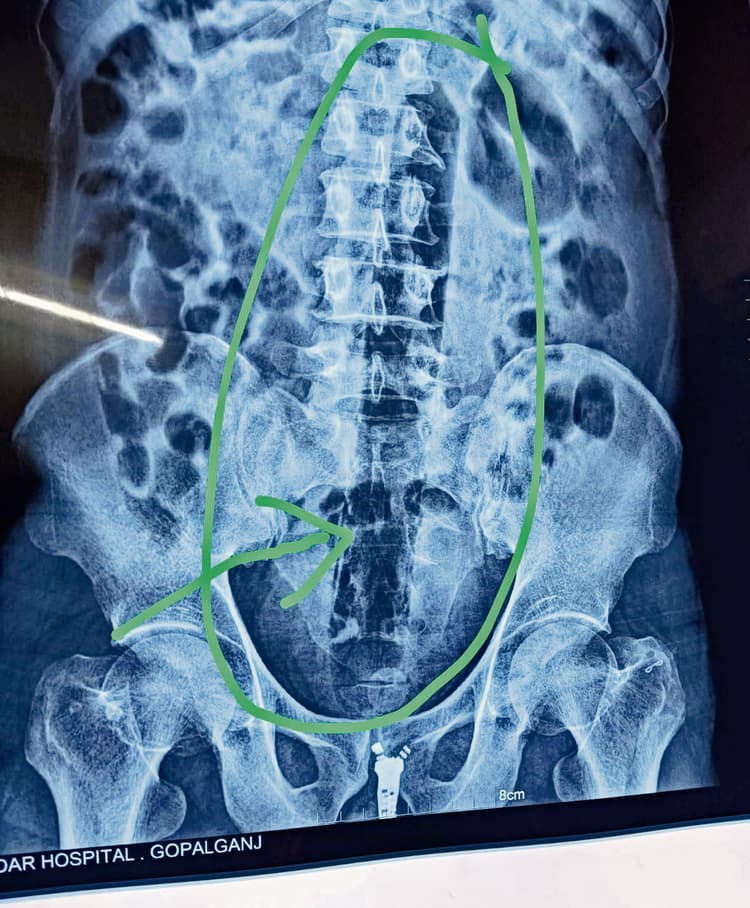

गोपालगंज. गोपालगंज के चनावे मंडल कारा में बंद 45 वर्षीय एक विचाराधीन कैदी ने हैरान करनेवाला कारनामा किया है. कैदी ने अपने गुप्तांग में एक फुट लंबा प्लास्टिक का पाइप डाल लिया. पेट में तेज दर्द होने पर कैदी ने इसकी सूचना जेल कर्मियों को दी, जिसके बाद जेल के अस्पताल में उसे ले जाया गया. हालत बिगड़ने पर कैदी को सदर अस्पताल रेफर कर दिया गया. सोमवार की रात इमरजेंसी वार्ड में भर्ती कराया गया, जहां मेडिकल बोर्ड की टीम ने इलाज शुरू किया. मेडिकल बोर्ड ने एक्सरे जांच करायी, तो रिपोर्ट में कैदी के पेट में एक फुट लंबा पाइप होने का पता चला. बिना ऑपरेशन पाइप नहीं निकल सकेगा, इसलिए डॉक्टरों की टीम ने बेहतर इलाज के लिए पीएमसीएच रेफर कर दिया. वहीं, कैदी ने ऐसा क्यों किया, इसका खुलासा नहीं हो सका है. एक फुट लंबा पाइप किया इंसर्ट : मेडिकल बोर्ड के सदस्य और कैदी का इलाज कर रहे सदर अस्पताल के चिकित्सक डॉ विमान केसरी का कहना है कि एक्सरे जांच रिपोर्ट में साफ नजर आया कि रीढ़ की हड्डी के पास एक लंबा पाइप के आकार जैसा वास्तु फंसा हुआ है. इसकी लंबाई तकरीबन एक फुट तक और मोटाई एक इंच से आसपास होने की संभावना है. डॉक्टर ने कहा कि कैदी ने खुद से पाइप को इंसर्ट करने की बात बतायी है. कैदी ने ऐसा क्यों किया, इसके बारे में उसने कुछ नहीं कहा है. डॉक्टर ने कहा कि सदर अस्पताल में इतना बड़ा ऑपरेशन करने के लिए तत्काल इंतजाम नहीं हो सकेगा, इसलिए चिकित्सकों की बोर्ड ने कैदी को बेहतर इलाज के लिए पीएचसीएच रेफर किया गया है. कड़ी सुरक्षा के बीच जेल की एंबुलेंस से कैदी को लाया गया था और सदर अस्पताल से पीएमसीएच रेफर किया गया है. जेल के सूत्रों ने बताया कि बरौली थाना क्षेत्र का रहनेवाला विचाराधीन कैदी हत्या के प्रयास के एक मामले में चनावे मंडल कारा में बंद है. रविवार की रात उसने अपने गुप्तांग में प्लास्टिक का पाइप डाल लिया. उसके बाद उसने पाइप को खुद से निकालने की कोशिश की. तब पाइप और भी अंदर की ओर चला गया. इसके बाद परेशानी बढ़ने लगी और उसने मंडल कारा के कर्मियों को इसकी सूचना दी. सोमवार को पूरे दिन मंडल कारा में ही उसका इलाज हुआ. हालत नहीं सुधरने पर बेहतर इलाज के लिए सदर अस्पताल के इमरजेंसी वार्ड में भर्ती कराया गया, जहां अस्पताल प्रशासन ने मेडिकल बोर्ड का गठन कर कैदी का इलाज शुरू कराया मेडिकल बोर्ड ने भी देर रात पीएमसीएच रेफर कर दिया.